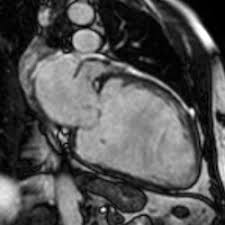

Die magnetresonanztomographie (mrt) spielt eine wichtige rolle für die diagnose. Vor allem störungen der pumpfunktion und der bewegungen der herzwand können genau untersucht werden. Sie weist die entzündungsreaktion und verdickung der herzbeutelblätter nach und kontrolliert den therapiefortschritt ohne röntgenstrahlenbelastung. Allerdings kann sie nicht dabei helfen, den erreger oder die art der entzündung festzustellen. Man findet örtlich im herzmuskel schwellungen, gewebszerstörungen oder vernarbungen. Ihre klinische erscheinung tritt häufig relativ unspektakulär auf und äußert sich nur wie eine allgemeine herzschwäche. Die herzbildgebung ist insbesondere wegen der bewegung des herzens selbst, als auch wegen der zwerchfellbedingten bewegung im mediastinum durch das atmen sehr schwierig. Je eingeschränkter die pumpfunktion ist, desto stärker ist die entzündung des herzmuskels. Allerdings kann sie auf niedrigem level auch unsichtbar sein. Die entzündungswerte im blut können ebenfalls aufschluss geben. Ein mrt des herzens ist vor allem dazu geeignet, die schwere der herzmuskelentzündung zu charakterisieren. Die schonung sollte solange beibehalten werden, bis der arzt wieder grünes licht gibt. Die besten anhaltspunkte für krankhafte vorgänge im herzmuskel liefert die kernspinuntersuchung.

So kann die gesamte funktionsfähigkeit der herzmuskulatur ebenso wie. Herz mrt bei myokarditis (herzmuskelentzündung) mrt mit herzschrittmacher? Da beim mrt keine röntgenstrahlung zum. Neben dem ekg kann auch eine magnetresonanztomografie (mrt) mit kontrastmittel aufschluss über entzündete herzareale geben. Auch die kraft, die das herz aufbringen kann, wird in einem mrt gemessen. Vorteile der magnetresonanztomographie des herzens. Die magnetresonanztomographie (mrt) spielt eine wichtige rolle für die diagnose. Handelt es sich um eine virusbedingte herzmuskelentzündung, stehen die chancen auf eine vollständige heilung relativ gut.

Ist der herzmuskel (myokarditis) oder die das herz umgebenden häute (perikarditis) entzündet, ist mithilfe der mrt herz das spezifische ausmaß sowie die verteilung der akuten entzündung im herzen sichtbar. Nicht jede myokarditis (herzmuskelentzündung) muss behandelt werden. Die darstellung des herzens ist besonders schwierig, da es sich in vielen richtungen teils schnell bewegt. Herz mrt bei myokarditis (herzmuskelentzündung) mrt mit herzschrittmacher? Im vordergrund steht hier die körperliche schonung. Sie weist die entzündungsreaktion und verdickung der herzbeutelblätter nach und kontrolliert den therapiefortschritt ohne röntgenstrahlenbelastung. In den vergangenen jahren hat die untersuchung hierzu weiter an bedeutung zugenommen. Die entzündungswerte im blut können ebenfalls aufschluss geben. Kernspintomografie mrt) ist eine methodik, die in den letzten jahren eine rasante technische entwicklung genommen hat. Allerdings kann sie auf niedrigem level auch unsichtbar sein. In der akuten phase ist eine herzmuskelentzündung auch im mrt erkennbar, wasser im herzmuskel deutet auf eine entzündung hin. Es folgt eine messung von puls und blutdruck, um entwaige abweichungen festzustellen. Damit können schweregrad und heilungsaussichten einer herzmuskelentzündung beurteilt werden.